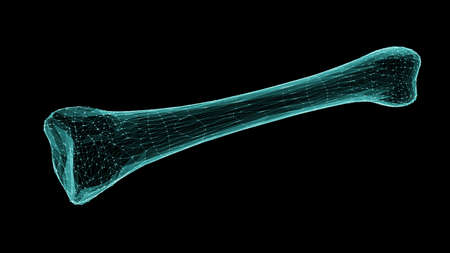

Human skeleton anatomy Fibula Bone 3D Rendering For Medical Concept

Human skeleton anatomy Fibula Bone 3D Rendering For Medical Concept

Human skeleton anatomy Fibula Bone 3D Rendering For Medical Concept

3D wireframe of a human bone isolated on black background. 3D illustration.